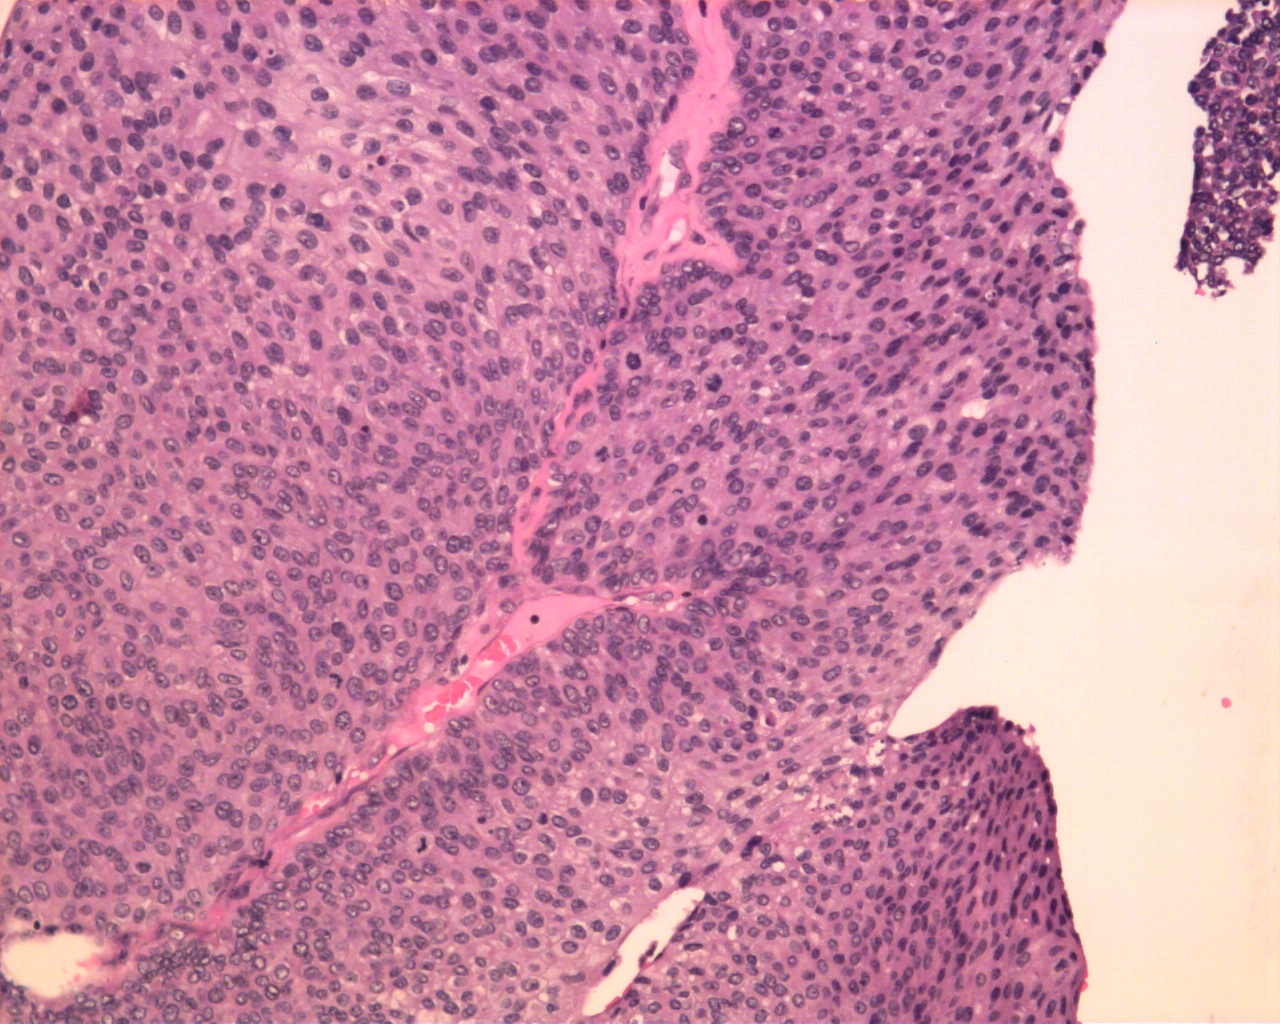

Consensus grade: Low-grade papillary urothelial carcinoma (LG-PUC)

User Diagnosis Difficulty Comment

Pathologist 1 Low-grade papillary urothelial carcinoma (LG-PUC) Typical

Pathologist 2 Low-grade papillary urothelial carcinoma (LG-PUC) Typical

Pathologist 3 Low-grade papillary urothelial carcinoma (LG-PUC) Borderline higher

Pathologist 4 High-grade papillary urothelial carcinoma (HG-PUC) Borderline lower

Pathologist 5 Low-grade papillary urothelial carcinoma (LG-PUC) Typical

Mostly inverted

Pathologist 6 Low-grade papillary urothelial carcinoma (LG-PUC) Typical

Pathologist 7 High-grade papillary urothelial carcinoma (HG-PUC) Borderline lower

Pathologist 8 Low-grade papillary urothelial carcinoma (LG-PUC) Typical

Pathologist 9 Low-grade papillary urothelial carcinoma (LG-PUC) Typical

Pathologist 10 Low-grade papillary urothelial carcinoma (LG-PUC) Typical

Pathologist 11 Low-grade papillary urothelial carcinoma (LG-PUC) Borderline higher

Pathologist 12 Low-grade papillary urothelial carcinoma (LG-PUC) Typical

Pathologist 13 Low-grade papillary urothelial carcinoma (LG-PUC) Bordering on higher

Pathologist 14 High-grade papillary urothelial carcinoma (HG-PUC) Bordering on lower

Pathologist 15 Low-grade papillary urothelial carcinoma (LG-PUC) Typical

Pathologist 16 Low-grade papillary urothelial carcinoma (LG-PUC) Bordering on higher

Pathologist 17 Low-grade papillary urothelial carcinoma (LG-PUC) Typical

Pathologist 18 Low-grade papillary urothelial carcinoma (LG-PUC) Typical

Pathologist 19 High-grade papillary urothelial carcinoma (HG-PUC) Typical

poor quality low power

Pathologist 20 Low-grade papillary urothelial carcinoma (LG-PUC) Typical

Pathologist 21 Low-grade papillary urothelial carcinoma (LG-PUC) Typical

Pathologist 22 High-grade papillary urothelial carcinoma (HG-PUC) Bordering on higher

Pathologist 23 Low-grade papillary urothelial carcinoma (LG-PUC) Typical

Pathologist 24 High-grade papillary urothelial carcinoma (HG-PUC) Bordering on lower

Case description (by case creator):